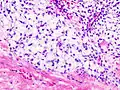

Histopathologic image of chondrosarcoma of the chest wall. Surgical resection of recurrent mass. H & E stain. | |